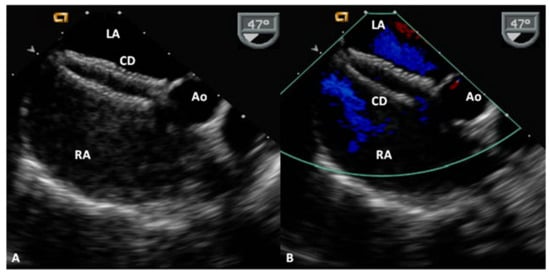

5.4. Coronary Sinus ASDs